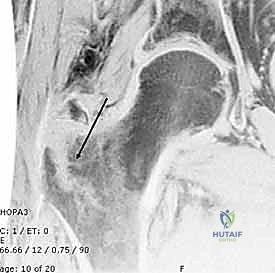

التصوير الطبي المتقدم

- التصوير بالرنين المغناطيسي (MRI): يُستخدم نادراً في هذه الحالات، إلا إذا كان هناك شك في وجود "كسر خفي" (Occult Fracture) لم يظهر بوضوح في الأشعة السينية ولكن المريض يعاني من آلام شديدة متوافقة مع الكسر.